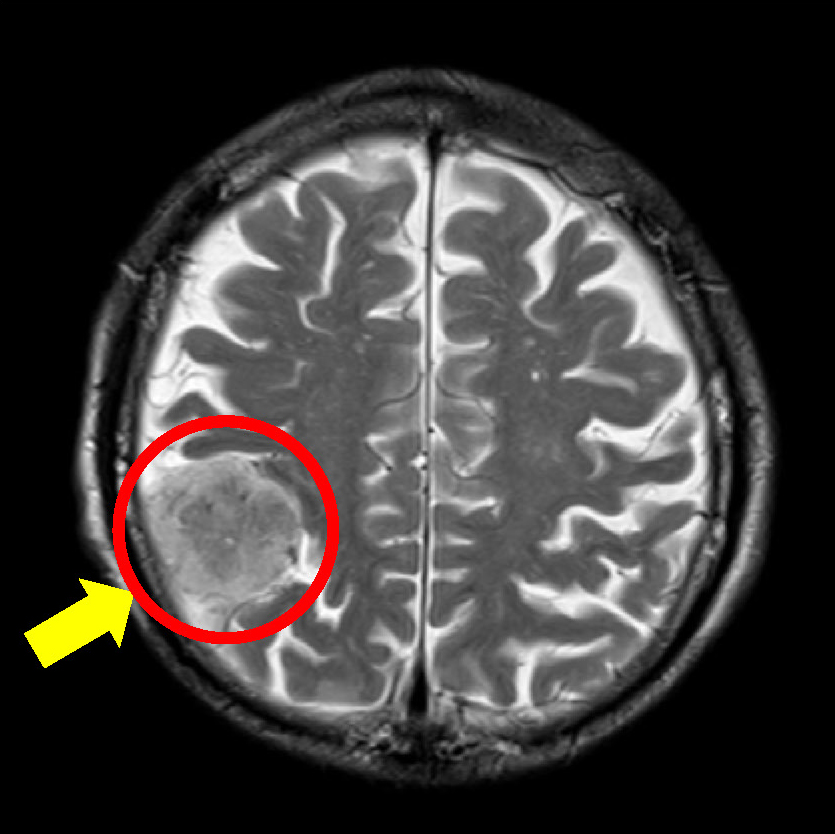

頭部MRI検査での1例

頭部MRI検査とは、脳の断面画像を撮影する検査です。

脳の梗塞・出血・萎縮・腫瘍性病変などを発見することが可能です。

脳腫瘍(髄膜腫)

髄膜腫とは、脳やその周りにある髄膜にできた腫瘍のことです。ほとんどの場合が良性腫瘍ですが、まれに悪性腫瘍の場合もあるので、注意が必要です。また、症状がない場合もあり、気づかないうちに大きくなると、まわりの脳神経に影響を与え、頭痛や歩きづらさ、麻痺、失語など様々な症状が現れます。男性に比べて、女性の方が多いのも特徴の1つです。